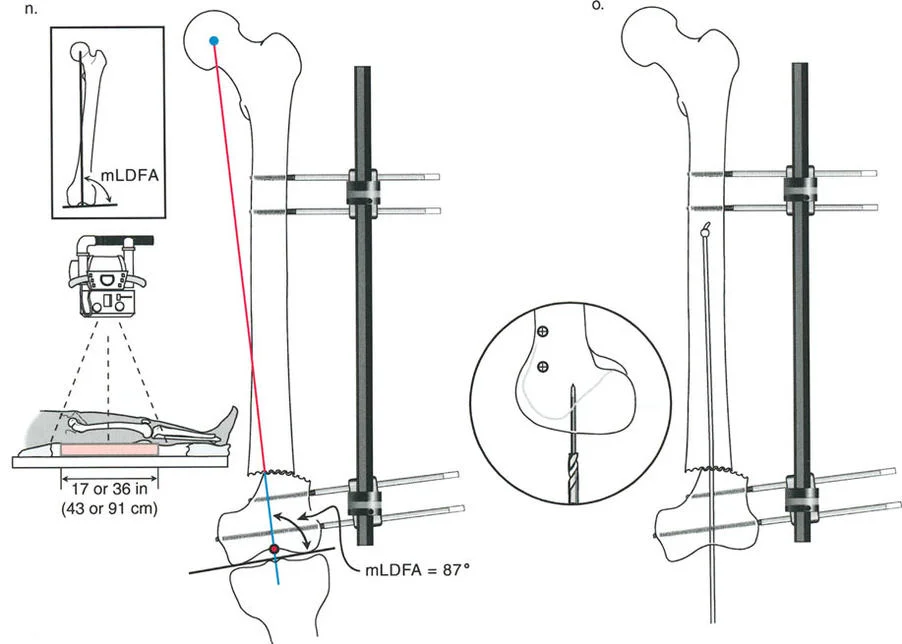

2. التصوير الشعاعي المتقدم:

تُعد الأشعة السينية هي الأداة الأساسية لتشخيص هذه التشوهات، ولكنها تتطلب تقنيات خاصة:

الأشعة السينية الكاملة للطرف (Full-Length Standing X-rays):

- يتم التقاط هذه الأشعة للمريض وهو واقف لتحمل الوزن، وتشمل العظم المصاب بالكامل بالإضافة إلى المفصلين أعلاه وأسفله (مثل الورك والركبة والكاحل للساق).

- تُؤخذ هذه الأشعة في وضعين رئيسيين: الأمامي الخلفي (AP) والجانبي (Lateral).

- أهميتها: تسمح هذه الصور للدكتور هطيف بتقييم المحور الميكانيكي للطرف بالكامل وتحديد مدى انحرافه، وقياس زوايا الانحراف وحجم الانزياح بدقة.

بمجرد الحصول على صور التصوير الشعاعي عالية الجودة، يقوم الأستاذ الدكتور محمد هطيف بإجراء تحليل هندسي دقيق باستخدام مبادئ الدكتور بالي:

- رسم المحاور: يتم رسم خطوط المحور الوسطي للعظم (mid-diaphyseal axis lines) للأجزاء القريبة والبعيدة من العظم المصاب على كل من الأشعة السينية الأمامية الخلفية والجانبية.

- تحديد مركز دوران الانحراف (CORA) أو نقطة الانحراف-الانزياح (a-t point): هذه هي النقطة التي تتقاطع عندها خطوط المحور، وتُعد "القمة الحقيقية" للتشوه. تحديدها بدقة أمر بالغ الأهمية لتخطيط مكان قطع العظم.

- قياس الانحراف والانزياح: تُستخدم قياسات دقيقة لتحديد حجم الزاوية (الانحراف) ومقدار التحرك الجانبي (الانزياح).

- تقييم انحراف المحور الميكانيكي (MAD): يُحسب مدى انحراف المحور الميكانيكي عن مركزه الطبيعي في الركبة.